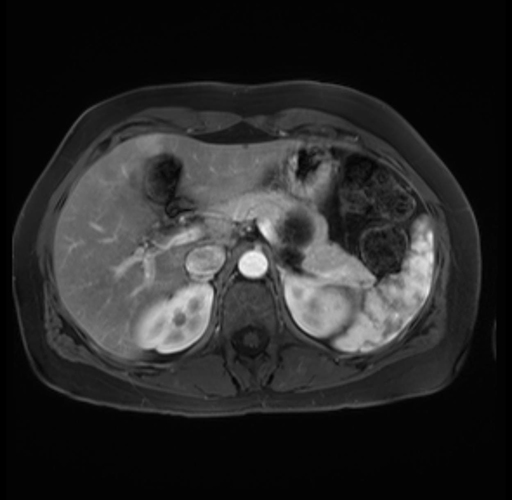

Imaging Analysis

Look through the patient's CT scan to identify any areas of concern for the necessary procedure.

Based on your CT findings, which issue(s) are present and would give reason for "planned slowing down moment(s)" in this case?